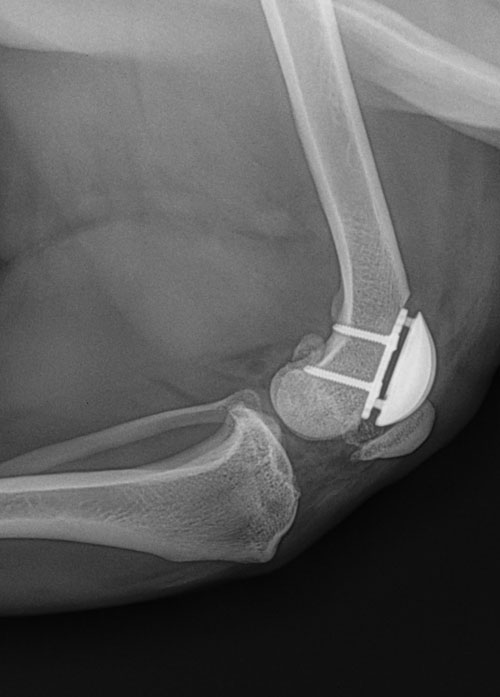

Mit unserer langjährigen Expertise und unserer erstklassigen Klinikausstattung sind wir in der Lage, Form- oder Funktionsfehler des Stütz- und Bewegungsapparates, also der Knochen, Gelenke, Muskeln und Sehnen, zu korrigieren. Hierzu gehören Knochenbrüche (Frakturen), zum Beispiel durch Unfälle, Stürze oder Bissverletzungen, oder Lockerungen (Luxation) bzw. Erkrankungen der Gelenke, Muskeln und Sehnen. Auch angeborene Deformationen der Knochen oder Gelenke, zum Beispiel Hüftdysplasien oder eine Verletzung oder Fraktur der Kniescheibe (Patella), können von uns professionell versorgt werden.

Von uns häufig durchgeführte Eingriffe beinhalten:

- Osteosynthesen von Frakturen

- Korrekturen von Knochendeformationen (inkl. Ilizarov)

- Hüftgelenkprothesen

- Kreuzbandoperationen wie TPLO (Tibial Plateau Leveling Osteotomy) oder TTA (Tibial Tuberosity Transposition)

- Gelenksspiegelungen (Arthroskopie)

und viele weitere für Ihr Tier notwendige orthopädische Operationen.

Für die Versorgung von Frakturen verwenden wir moderne Implantate, konventionelle und winkelstabile Knochenplatten, Fixateur Externe aus Karbon – eine Haltevorrichtung, die bei der Erstversorgung von Knochenbrüchen angewandt wird – Titanstangen sowie Ilizarov-Ringfixateure.